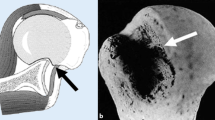

Engaging Hill-Sachs defects of the humeral head are well documented risk factors for recurrent glenohumeral shoulder instability and failed anterior shoulder stabilization [1–3]. Several studies have shown that an engaging Hill-Sachs defect treated with Bankart repair alone is associated with a high re-dislocation rate [1, 3–5]. Different surgical options have been described in order to address this problem: Retrograde disimpaction, osteochondral allograft, humeral osteotomy and partial or complete replacement of the humeral head [6–9].

Connolly first described an open procedure of filling a Hill-Sachs defect with infraspinatus and capsule tenodesis, together with a Bankart repair [10]. This technique works by converting an intra-articular defect into an extra-articular one and thus preventing the defect from engaging at the anterior glenoid rim. Furthermore, there is a check-rein effect on the humeral head, effected by the fixed infraspinatus tendon and posterior capsule. Wolf et al. termed the procedure remplissage when they performed the procedure arthroscopically, placing suture anchors into the valley of the Hill-Sachs defect and passing the sutures posteriorly through the infraspinatus tendon and capsule [11]. Cadaveric studies have shown that medium sized Hill-Sachs lesions without glenoid bone loss can be successfully treated with the remplissage procedure if combined with Bankart repair [12, 13]. In recent years, clinical studies have already reported good functional outcomes with minimal loss of shoulder range of motion [14–16]. Although, filling of the Hill-Sachs defect by infraspinatus tendon and capsule on post-operative scans has been demonstrated [17], there are no studies in the literature investigating the amount of infraspinatus tendon coverage over the defect zone produced by different techniques.

Preparation of Bankart lesion and Hill-Sachs defect

Since several studies described Hill-Sachs defects ≥25 % to be relevant for recurrent glenohumeral instability a 30 % defect size was chosen [2, 20]. The standardized Hill-Sachs defects were created using the method described by Sekiya et al. [20] An extended horizontal capsulotomy was performed to expose the antero-inferior rim of the glenoid and the posterior aspect of the humeral head. A line was drawn on the humeral head parallel to the anterior-inferior glenoid rim, representing the defect orientation. The humeral head diameter was measured with a caliper [mm]. A defect equivalent to 30 % of the postero-lateral humeral head was marked on the humeral head and created with an oscillating saw. The positions of suture anchors were marked in the valley of the defect, at the junctions of one-thirds of the defect length. The defect size, shape and suture anchor location were then duplicated on a template. Bankart lesions were created by sharp dissection of the labrum from the anterior-inferior glenoid rim. After defect creation the capsulotomy was anatomically closed without any over-tightening and/or overlap. Thus careful attention was paid to maintain the initial capsular tension. Finally subscapularis and teres minor muscles were tagged together.